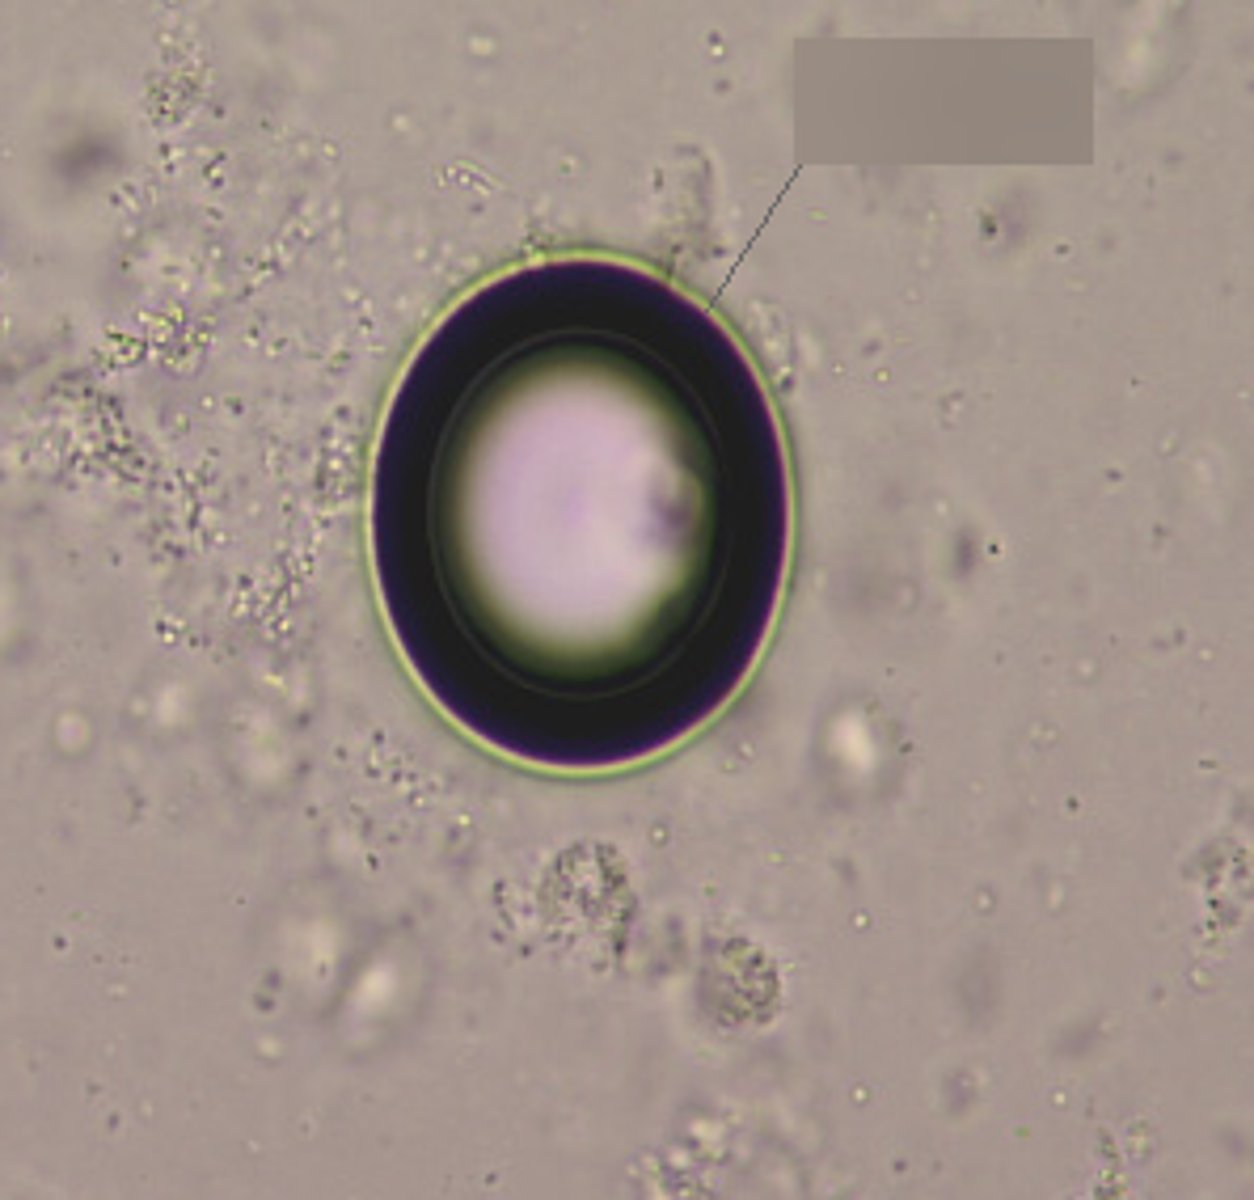

cholesterol crystals

Associated with nephrotic syndrome

Refracts and shows bright cut crystals

Seen with fatty casts